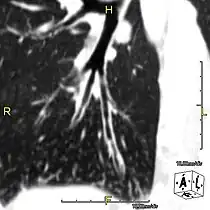

Sagittal CT image showing "tree in bud" appearance of mucous impaction in distal small airways related to primary ciliary dyskinesia -

CT image showing dilated and thickened medium-sized airways (bronchiectasis) in a patient with Kartagener syndrome -

Oblique sagittal CT image showing lower lobe cylindrical bronchiectasis -